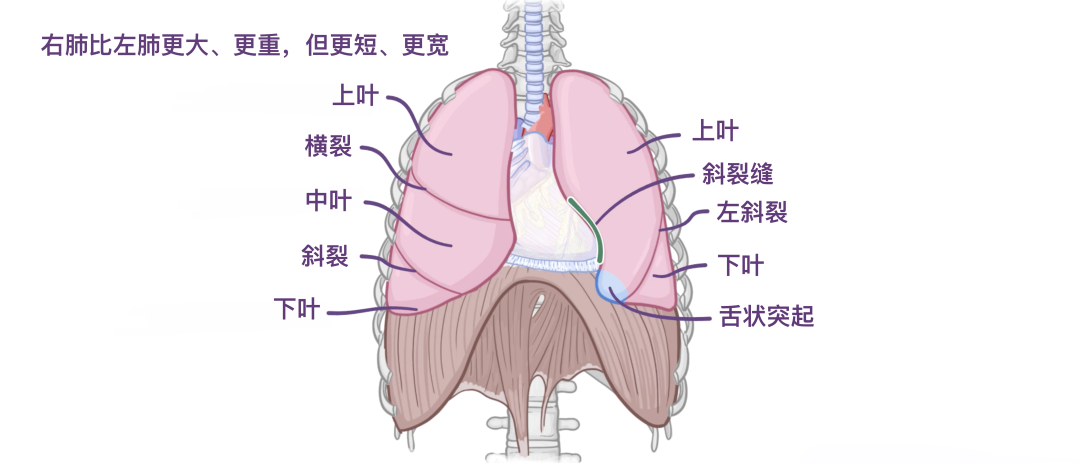

右肺比左肺更大、更重,但更短、更宽,因为横膈膜的右圆顶更高,心脏和心包更靠左。右肺被横裂和斜裂分为上、中、下三叶,在肺的各个表面都可以看到。另外一侧,左肺有一个左斜裂,在所有表面上都可以看到,并将左肺分为上叶和下叶两个叶。

同样在左肺,前缘有一个很深的心脏切迹,这是由于心脏向左偏斜造成的。这会在上叶的前下方留下印记,并形成一个称为小舌的舌状突起。小舌延伸至贲门切迹下方,呼吸时进出肋纵隔隐窝。